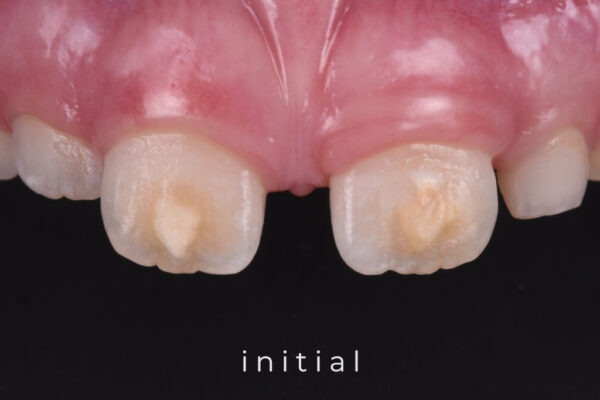

Did you start using ICON but did you have unpredictable results? This course will give you a better understanding of enamel defects, how to diagnose and treat them. There will be focus on the infiltration of both proximal and vestibular lesions. Combined with bleaching, micro-abrasion and cosmetic bonding there is a solid treatment protocol for all different situations, no matter how difficult.

- Different enamel defects that can occur, including:

- Demineralisation

- Hypomaturation

- Hypoplasia

- How to diagnose different enamdel defects

- Pre-eruptive hypomineralisations, including:

- Molar Incisor Hypomineralisations

- Infiltration and ways to optimise the esthetic result